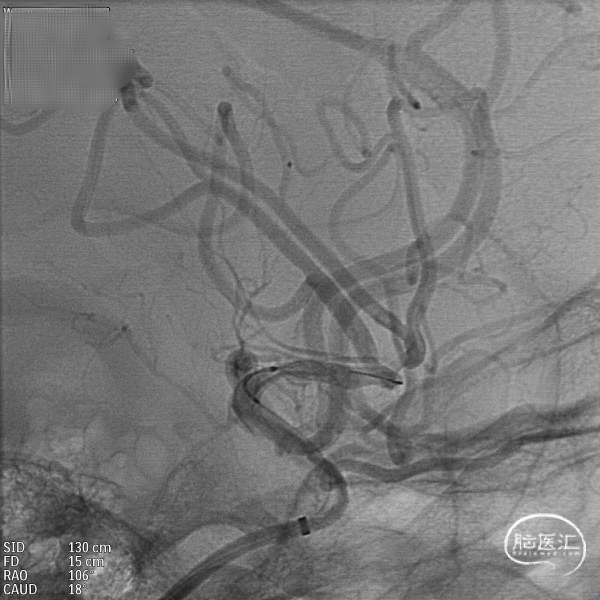

支架到位,远端打开(正侧位):4.75-20mm支架在大脑中动脉M1段打开,回撤至C6段远端锚定。支架释放过程中,轻柔推送支架系统,可见支架导管沿血管壁大弯侧走行,支架打开良好。

支架中段打开:

输送导丝及微导管回撤:释放至支架末端,减张系统,回撤支架导管,释放支架。沿支架推送杆,调节系统张力,将支架导管通过支架到达C7段。

支架内使用成襻微导丝进行按摩,使支架充分贴壁。

术后造影:支架覆盖两枚动脉瘤瘤颈,贴壁良好,瘤体内可见造影剂滞留。